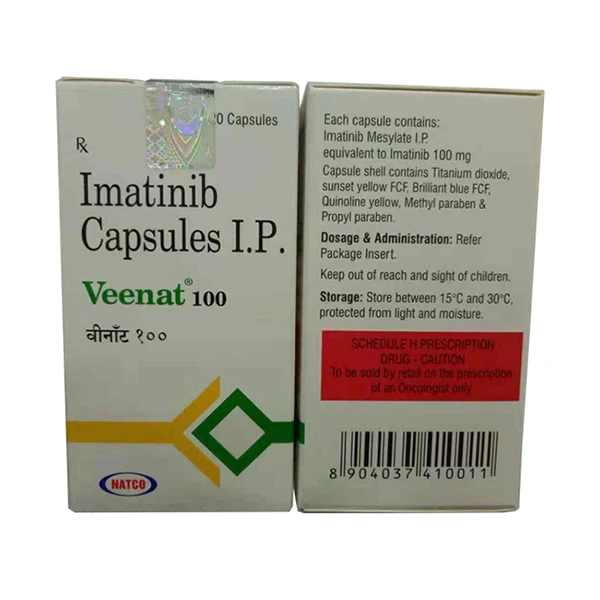

Cazanat 卡博替尼 Cabozantinib

卡博替尼(Cabozantinib)是一个多靶点的广谱抗癌药,能抑制的靶点包括:MET、VEGFR1/2/3、ROS1、RET、AXL、NTRK、KIT等至少9个。 目前,卡博替尼已经在肾癌、甲状腺癌、肝癌、软组织肉瘤、非小细胞肺癌、前列腺癌、乳腺癌、卵巢癌、肠癌等多种实体瘤中,证实了较好的治疗效果,对于骨转移的控制效果尤其突出。因其对于多种癌症的广泛有效性,卡博替尼被称为靶向药中的“万金油”,具有广谱抗癌能力。